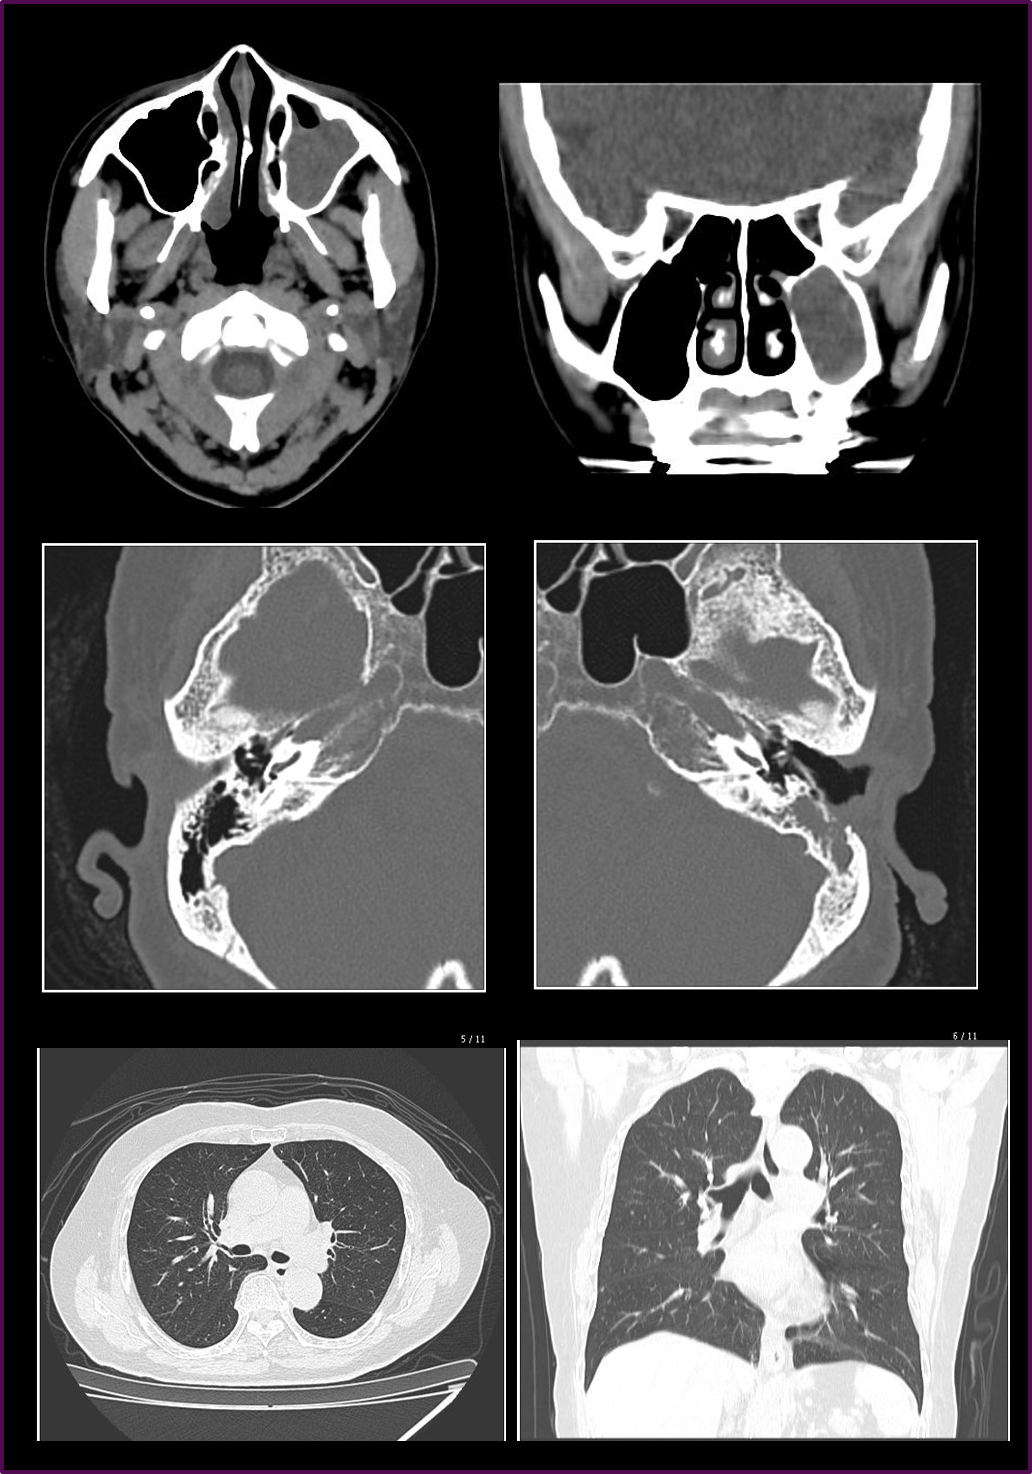

また、2スライスから16スライスになったことで、 アキシャル画像だけでなく、いわゆるMPR画像と言われるサジタル画像やコロナル画像などの画質も飛躍的に向上して、作成の頻度も増えました。

特に耳鼻科領域は内耳、副鼻腔、耳下腺など、アキシャル画像以外の断面も必要とすることが多いので、MPR画像の画質向上は有効で、かつこのMPR画像はとても簡便に作成できるので助かっています。

また、耳鼻科のため、頭部領域のCT撮影がほとんどですが、咽頭部・気管支などの病変確認のために胸部CT撮影も行います。

胸部全体でしたら10秒前後の息止めで検査を終了できますし、さらにMPR画像も容易にかつ 高画質に作成可能なので、診断する医師にとっても、検査を受ける患者様にとっても、非常に有用なCTと言えると思います。

cv_otaru_02_big.png

CT Revolution ACT 臨床画像